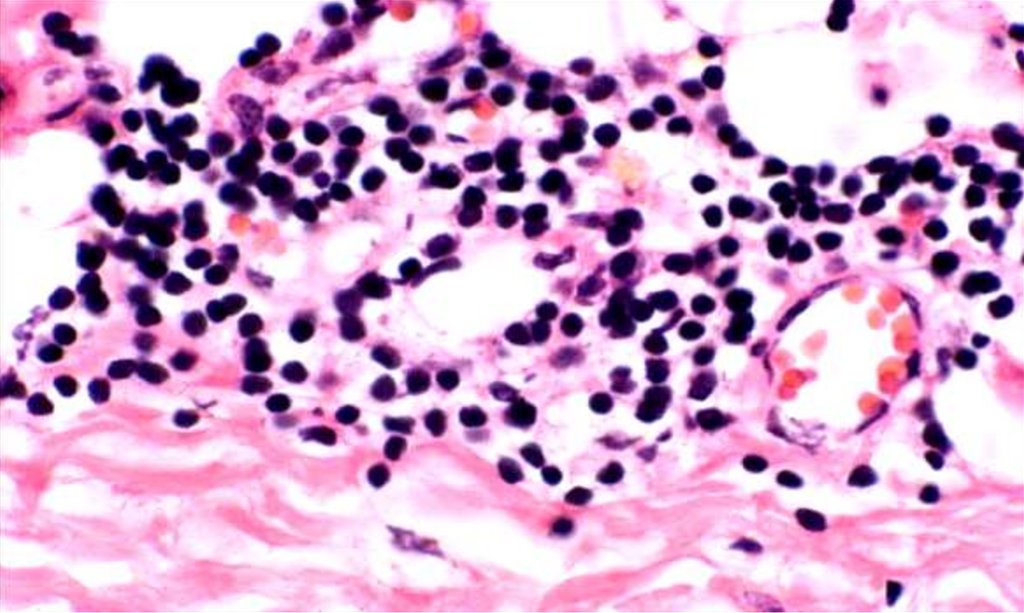

42. ЛЕПРА

• Mycobacterium leprae

• Отсутствие некроза

• Лепрозная гранулема

Лепрома

Лепрозные клетки Вирхова (лепрозные шары)

Mycobacterium leprae в макрофагальном инфильтрате

при лепроматозной лепре